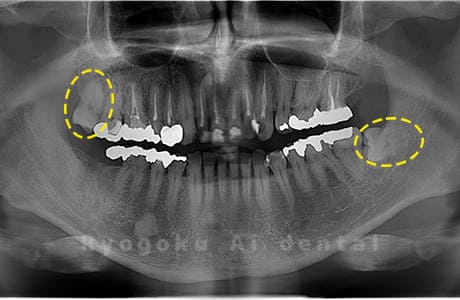

Case03

-

- 原因

- 上顎、下顎の親知らず

- 治療内容

- 上下4本の親知らずを抜歯したケースです。

<リスク・副作用>

手術後は痛み、腫れ、痺れなどの副作用が生じる場合があります。